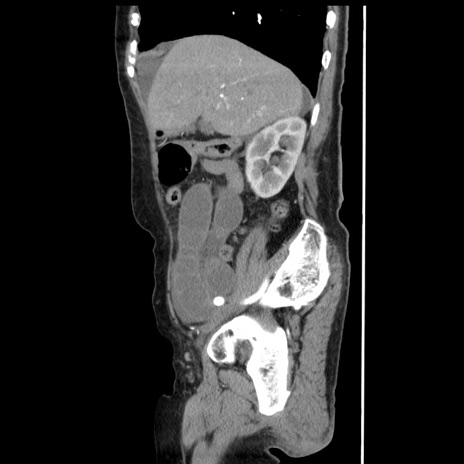

冠状断像

【症例】80歳代女性

【主訴】腹痛

【現病歴】8時間前から腹痛あり来院。

【既往歴】糖尿病、脂質異常症、子宮体癌にて子宮全摘術

【身体所見】意識清明・会話良好だが腹痛で苦悶様、全腹部にわたって反跳痛と圧痛あり

【データ】WBC 13600、CRP 0.14、LDH 224、CK 90